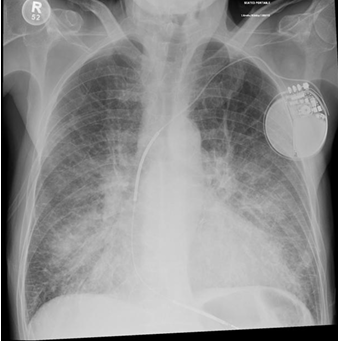

Cardiomegaly

Pulmonary Edema

Dextrocardia

Mitral Annulus Calcifications

Pacemaker Placement